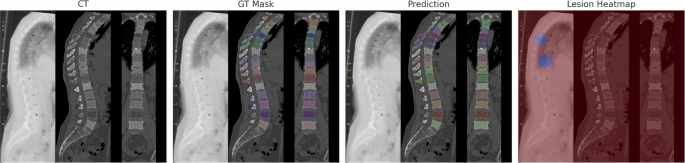

Figure 2 presents a set of representative qualitative results that comprehensively illustrate the performance of VertebraFormer across the three target tasks: vertebra segmentation, identification, and lesion detection. Each example is organized into four panels: (1) the original CT slice providing the raw anatomical context, (2) the ground-truth segmentation overlaid with vertebra IDs, (3) the predicted segmentation mask and identification labels produced by our model, and (4) the corresponding lesion detection heatmap.

(1) CT image, (2) ground-truth mask, (3) predicted segmentation, and (4) lesion heatmap. Arrows indicate the localization of the T11 Endplate defect, demonstrating the spatial alignment between the predicted lesion heatmap and the ground truth.

From the visual comparison, it can be observed that the predicted segmentation masks exhibit a high degree of spatial overlap with the ground-truth annotations, accurately delineating vertebral boundaries even in challenging regions such as the thoracolumbar junction and degenerated disks. The ID assignment remains consistent along the entire spine, effectively handling cases with partial vertebra visibility or irregular morphology, which are often challenging for conventional approaches.

In addition to segmentation and identification, the lesion detection heatmaps successfully localize clinically relevant abnormalities with precise spatial alignment. These heatmaps reveal subtle pathological patterns such as localized cortical thinning, vertebral fractures, and tumor infiltration, which are visually distinct from normal tissue regions. Such interpretability enables radiologists to rapidly pinpoint abnormal regions while preserving the broader anatomical context, reducing diagnostic ambiguity.